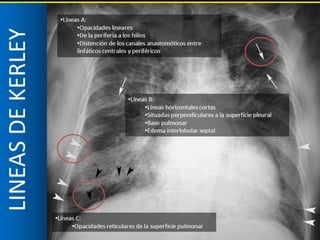

LÍNEAS DE

Se deben a engrosamiento de los septos interlobulares por

LÍNEA DE

APICALES

Septos profundos

engrosados

4 cm

Desde hilio hacia porciones

centrales,

sin alcanzar la pleura

Notorias en porciones

centrales y superiores

Goodman LR. Felson. Principios de Radiología Torácica. Un texto programado.3a Edición. España: Elsevier; 2009.

BASALES

Septos interlobares

periféricos engrosados

2cm

Paralelas, formando un

ángulo recto con pleura.

CENTRALES

Líneas entrecruzadas por

sobreposición de varias

líneas B

Reticulado opaco

representativo de líneas B

vistas de frente